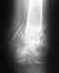

Снимок мне так и не дали, доктор разнервничался и сказал, чтобы я и лечить везла мужа туда, где собираюсь консультироваться, а так же у них не работает принтер, но это лирика. так же пояснил, у нас перелом лоджки и перелом первой трети берцовой кости со смещением, без аперации не обойтисьи предложили вбрать материал: русский и по ОМС плохой, польский чуть лучше, а если мы хотим по настоящему лечиться, то самый лучший шведский .Дали неделю на размышления и сбор денег.Вот мы и думаем, что же нам выбрать.Может В мне поясните и поможете с выбором